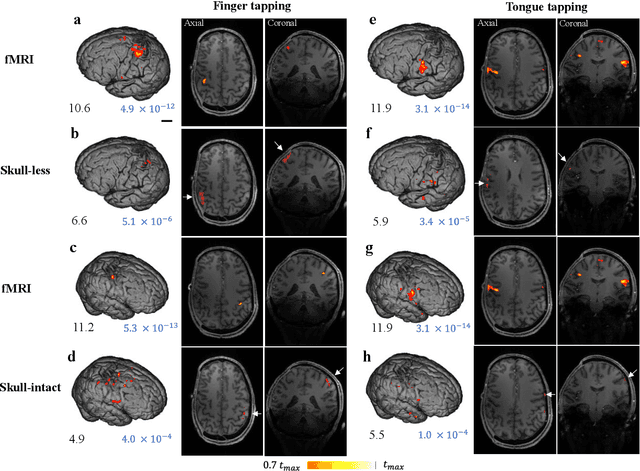

Abstract:Herein we report the first in-human transcranial imaging of brain function using photoacoustic computed tomography. Functional responses to benchmark motor tasks were imaged on both the skull-less and the skull-intact hemispheres of a hemicraniectomy patient. The observed brain responses in these preliminary results demonstrate the potential of photoacoustic computed tomography for achieving transcranial functional imaging.